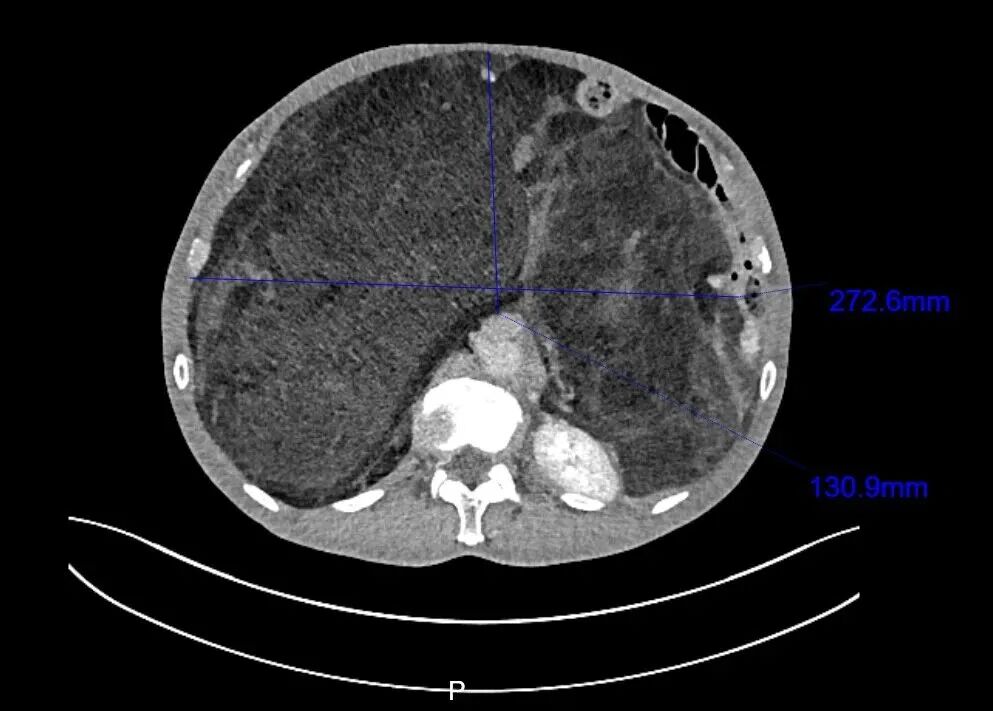

8月初,老邹慕名来到浙大二院肿瘤内科就诊。入院后,医生安排他做了腹部增强CT和肿瘤穿刺活检。腹部CT提示:巨大的肿瘤从左上腹一直延伸到右下腹及盆腔,最长径达40厘米,前后径也有20厘米,几乎“填满”了整个腹腔。肿瘤穿刺病理提示:腹膜后高分化脂肪肉瘤。

“从腹部CT上看,患者内脏器官已经被这个肿瘤挤压得明显移位了,小肠和胰腺被挤到了左上腹靠近膈肌的位置,右肾完全被肿瘤组织包绕,被挤压至身体左侧,原本在腹腔右侧的升结肠和阑尾被挤到了左侧腹腔。腹腔内几乎所有的脏器都改变了原有的位置。”焦裕荣医生说,“如果不选择手术,肿瘤会持续增大,上抬膈肌导致呼吸抑制;进入腹腔盆腔薄弱区域,导致腹股沟疝气等一系列并发症的发生。”